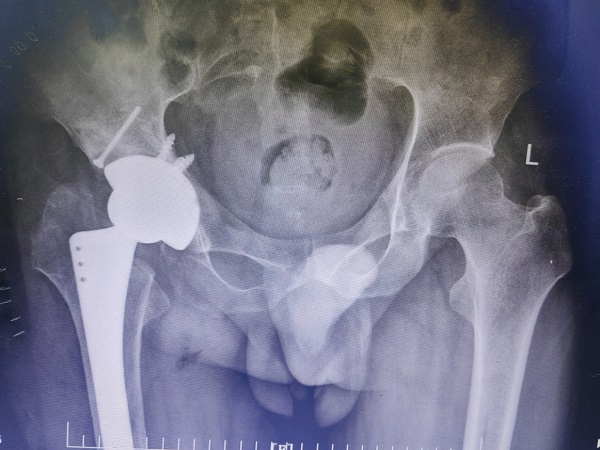

李师傅病程长,情况复杂,检查发现其骨盆倾斜,股骨头、颈部分缺如,髋臼严重骨缺损,髋关节半脱位,患肢短缩近6cm,髋关节周围软组织挛缩。手术难度大,髋部股神经、坐骨神经以及股动脉牵张损伤的风险很大,创伤骨科郭永良主任和王争刚主任医师经过充分术前讨论,制定出了细密的个性化手术方案,并与患者及家属充分交流和沟通。

为了顺利手术,在完善髋臼骨缺损的垫块、异体股骨头等结构性植骨材料、陶对陶全髋关节假体的准备后,郭永良主任医师主刀,王争刚主任医师等辅助,历时2小时,手术顺利完成。术后患者双下肢等长,无神经、血管损伤。目前术后三周,患者可扶拐逐渐负重下地行走,相信经过一段时间的康复和锻炼,李师傅可再次回归社会,恢复正常的生活和工作。